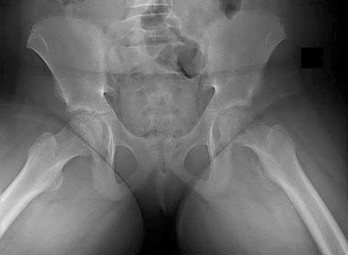

A 32-year-old male is brought to the trauma bay in hemorrhagic shock after a motorcycle crash. An anteroposterior radiograph of the pelvis demonstrates an APC-III injury. A pelvic binder is applied. To maximize reduction of the pelvic volume, at what anatomical landmark should the binder be centered?

Correct Answer: Greater trochanters

Explanation:

Pelvic binders should be centered over the greater trochanters to effectively close the pelvic ring and reduce pelvic volume. Placement over the iliac crests or ASIS can paradoxically widen the true pelvis or fail to achieve adequate reduction in an open-book pelvic injury.